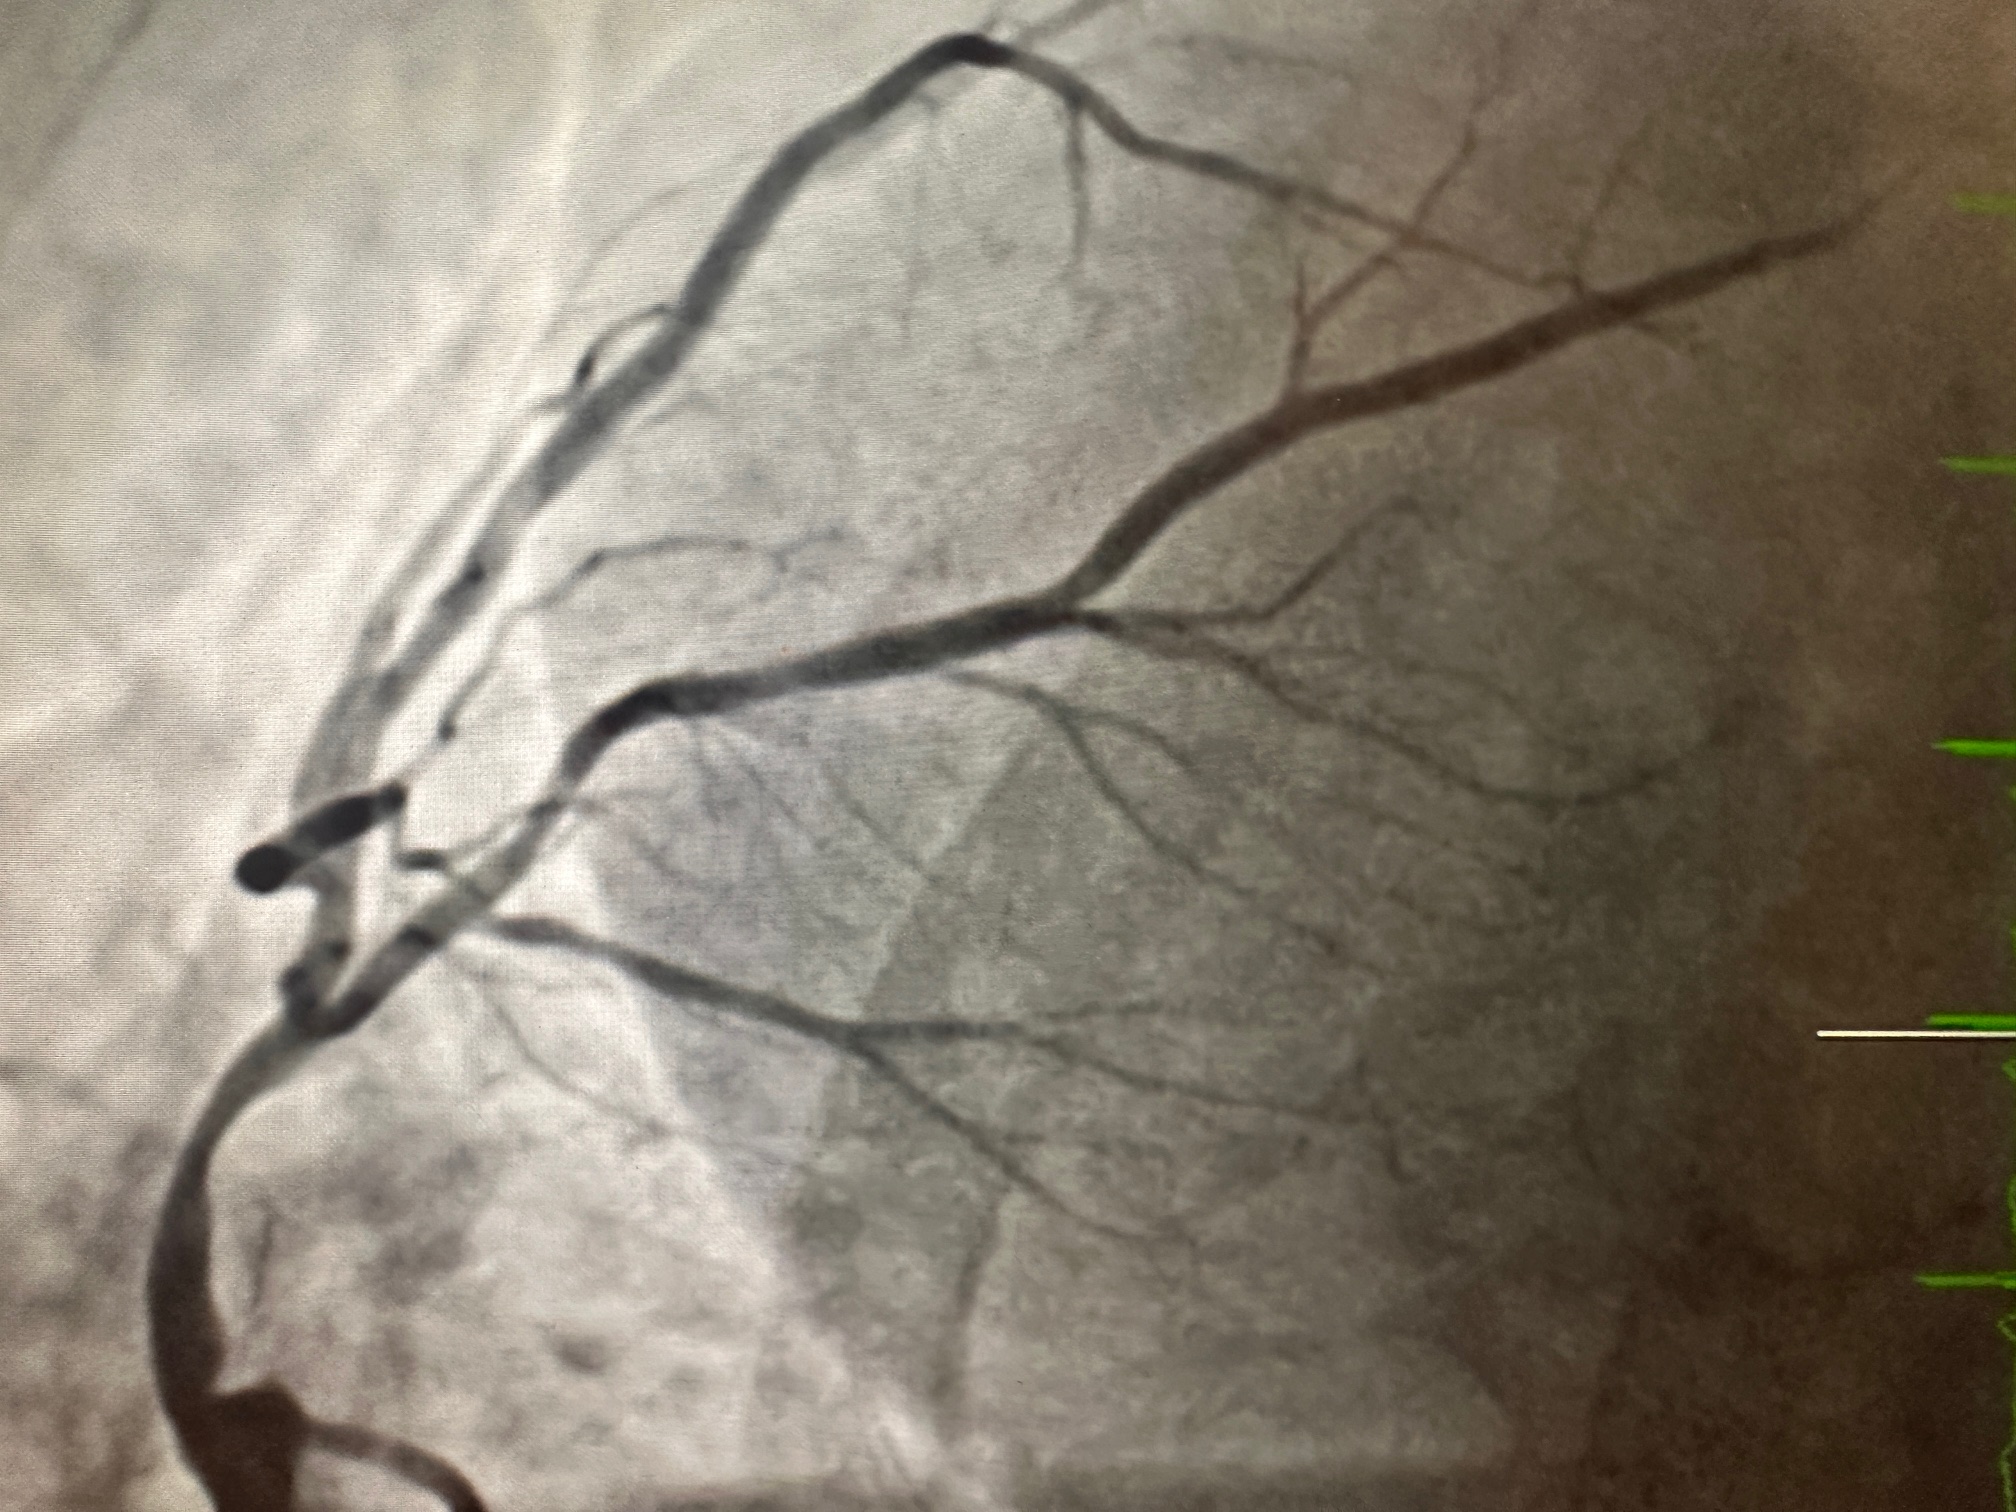

Relevant Catheterization Findings

Coronary Angiography:

Procedure: Ad hoc PCI to LM-proximal LAD.

- PCI:

- LM-Proximal LAD lesion treated with a drug-eluting stent (DES), achieving TIMI 3 flow post-PCI.